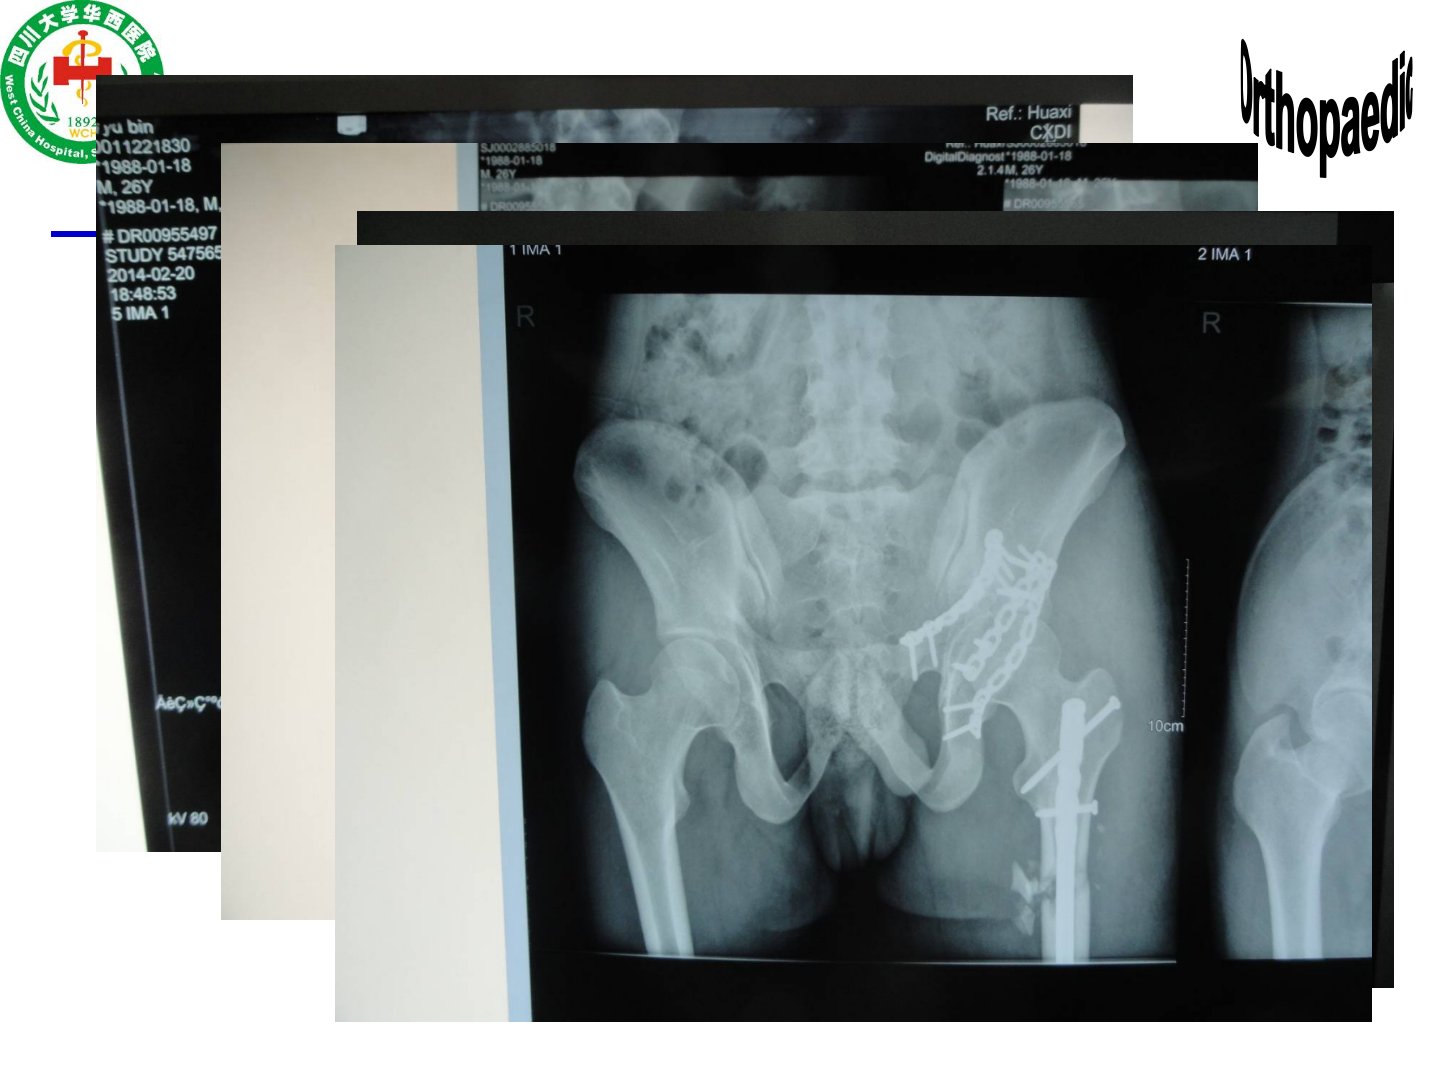

四肢骨折摘要本文由四川大学华西医院骨科黄富国介绍四肢骨折相关内容。骨折诊断需明确创伤部位、机制、时间、开放闭合情况、程度类型及并发症等。暴力机制影响骨折诊治与预后不同暴力类型(高处坠落伤、车祸伤等)有不同意义影像检查(X线、CT、MRI)对明确骨折情况、指导治疗和判断预后意义重大。骨折移位由暴力大小方向、肢体重力、肌肉牵拉导致会产生血管神经损伤等后果必须矫正的移位因骨折部位而异。骨折并发症包括骨折不愈、骨坏死、骨筋膜室综合征等。治疗原则为先保生命再保肢体最后保功能方式有非手术(复位手法、牵引、固定方式)和手术(固定方式多样)。文章还提出学习目的和要求包括掌握多种骨折的诊断治疗原则熟悉部分骨折并发症及处理了解另一些骨折的相关情况。此外详细介绍了肱骨、尺桡骨、桡骨远端、股骨、胫腓骨等部位骨折的解剖、病因、分类、临床表现、诊断及治疗原则并以患者男45岁车祸伤为例提出诊断、辅助检查、合并伤相关问题。